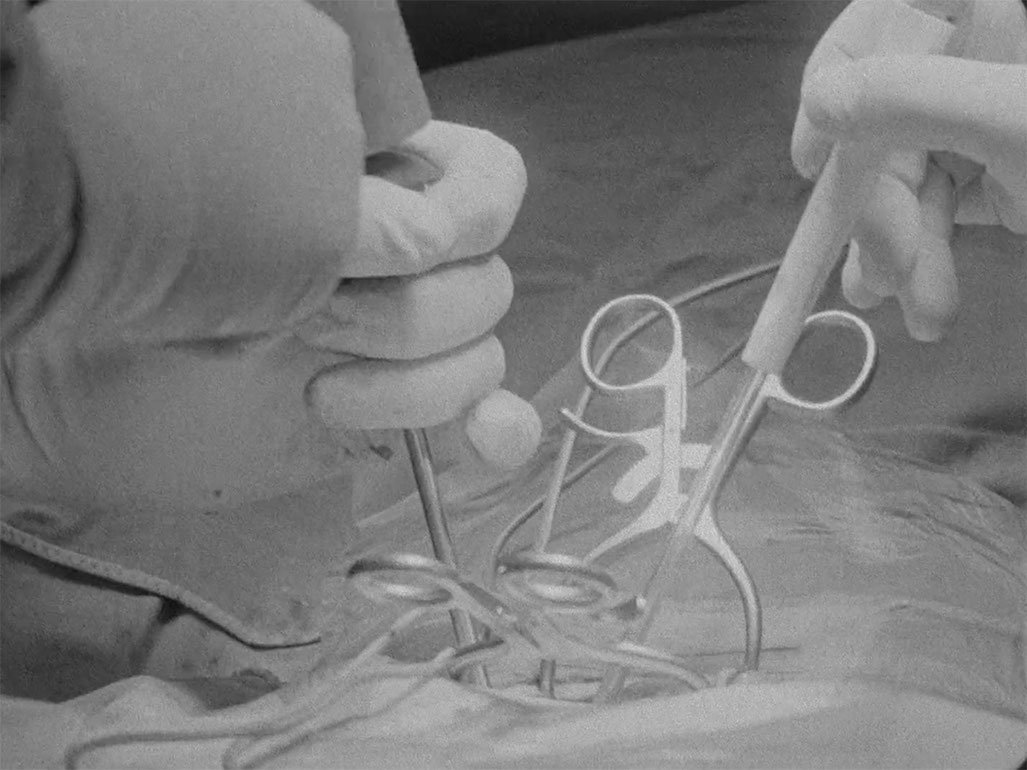

Matters of the Heart, a series of five, silent, black-and-white films of operations were shot with a 16mm Bolex film camera in the operating room: Heart, Stomach, Blood Flow, Vertebra, Eye/Hand. Two choreographies overlap: that of the surgeons and that of the intuitive-conceptual camera editing during the filming. The extremely concentrated material ends in several cases before the operation is over, rips open into white. Christina Lammer´s films require elaborate preparations: the artist and sociologist makes on site samples, sketches, and studies the time lapses with the digital Bolex. Together with all involved, she works out the concept and mutual trust: "The negotiation processes - not only with the patients who allow me to film their operations, but also with the entire hospital administration and the medical ethics commission - are, in fact, quite complex. I get along well with the patients. I ask for their consent, and give a detailed explanation of my intentions and how I handle the pictures. Since they are not personally recognizable in almost all of the operations, they gladly allow me to film in the operating room. I also visit the patients regularly as long as they are in the hospital. That is a part of it for me, and flows in the further film and video work intuitively or as experience. There is nothing uncomplicated about this form of film."(Ch.L.)

The skin as a linear border developed along with the bourgeois individual in the modern era; there were times when it was perceived as more permeable, as a porous mesh that is a potential opening. In Lammer´s films, hands covered in brightly colored gloves with shiny operating tools stake out the terrain, make contact with the fluids, tissues, bowels, and organs of the opened body - and unearth the "small, specific frissons" (W. Benjamin). Tactile qualities structure the gaze in this somatic contact zone. A precise cut, the pulsating movement of the hand in the depths of the body, sputtering blood, valiant gripping of an organ, threading hands, a tiny nerve - all of this in the fine, soft gray tones of the empathetic film material. (Madeleine Bernstorff)